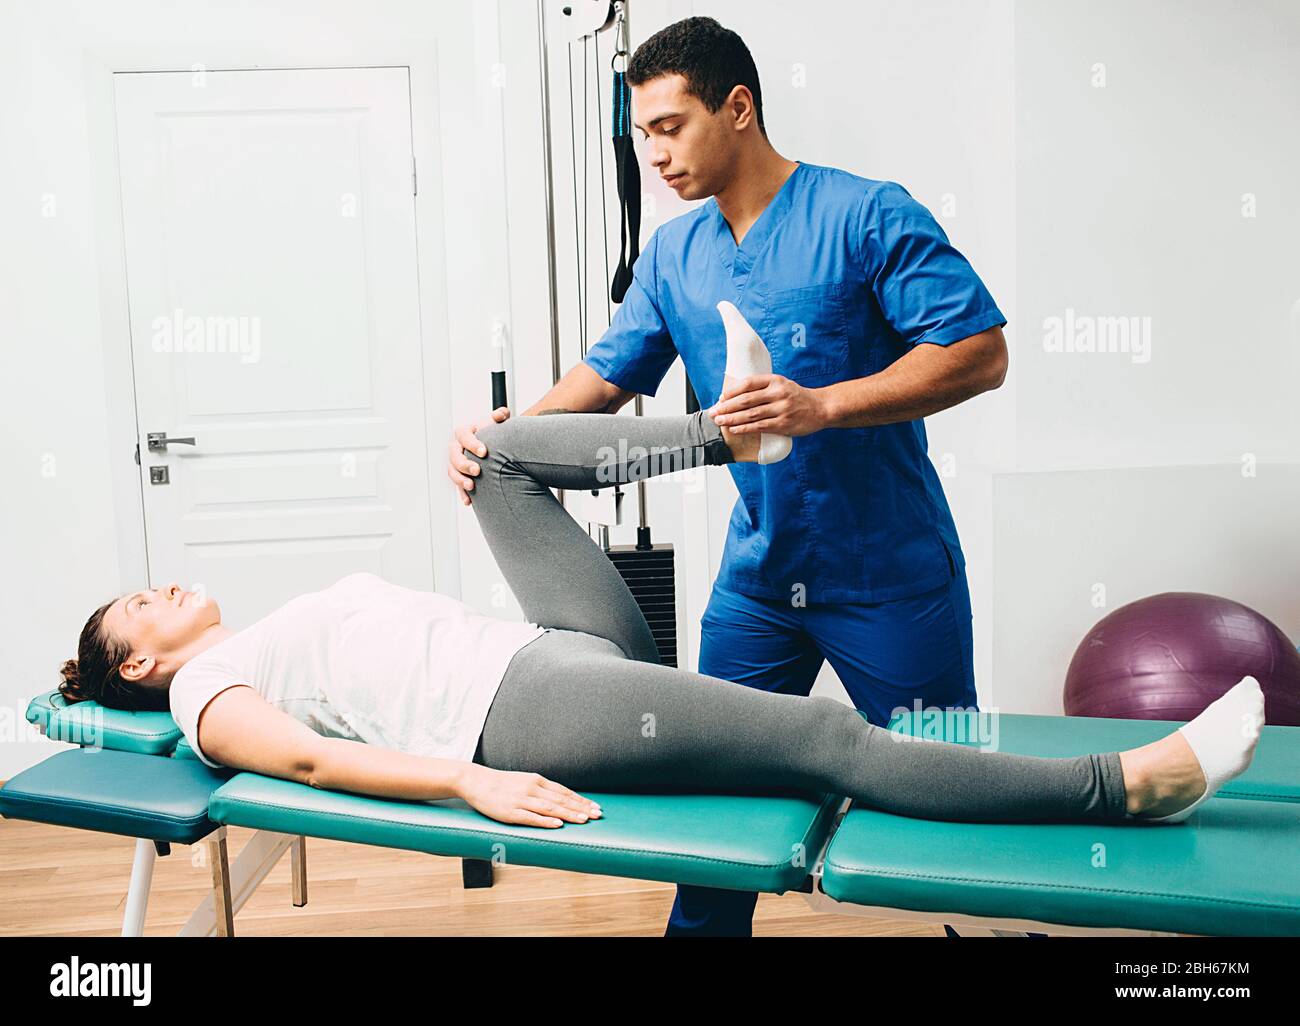

physiothérapeute faisant des muscles de jambe s'étirant vers le patient. Traitement du nerf sciatique d'une femme Banque D'Imageshttps://www.alamyimages.fr/image-license-details/?v=1https://www.alamyimages.fr/physiotherapeute-faisant-des-muscles-de-jambe-s-etirant-vers-le-patient-traitement-du-nerf-sciatique-d-une-femme-image354794264.html

physiothérapeute faisant des muscles de jambe s'étirant vers le patient. Traitement du nerf sciatique d'une femme Banque D'Imageshttps://www.alamyimages.fr/image-license-details/?v=1https://www.alamyimages.fr/physiotherapeute-faisant-des-muscles-de-jambe-s-etirant-vers-le-patient-traitement-du-nerf-sciatique-d-une-femme-image354794264.htmlRF2BH67KM–physiothérapeute faisant des muscles de jambe s'étirant vers le patient. Traitement du nerf sciatique d'une femme